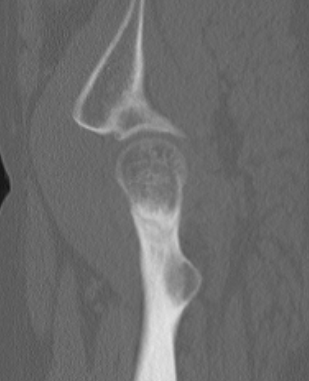

Femoral neck fracture on right in patient with coxa vara

Increased sclerosis at inferior neck Xray demonstrating incomplete fracture of the superior neck